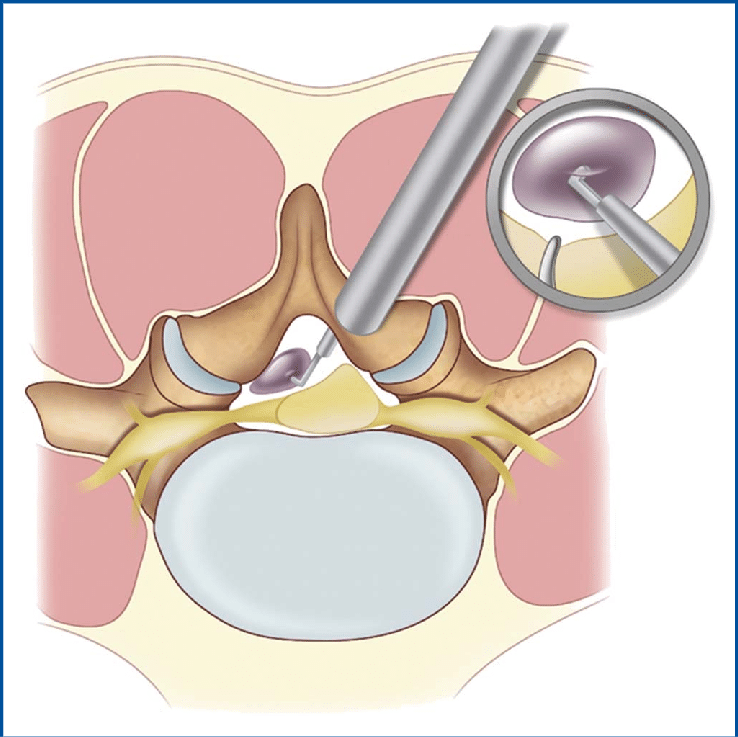

- Usunięcie torbieli: Przy użyciu technik mikrochirurgicznych możliwe jest precyzyjne i bezpieczne usunięcie torbieli.

- Minimalna inwazyjność: Dzięki wykorzystaniu mikroskopów i endoskopów zabiegi są mniej obciążające dla pacjenta i wymagają krótszej rekonwalescencji.

- Jeśli torbiel powoduje znaczny ucisk na struktury nerwowe lub metody zachowawcze nie przynoszą poprawy, konieczna może być interwencja chirurgiczna.

Dr. Damian Kocur specjalizuje się w technikach małoinwazyjnych, takich jak: